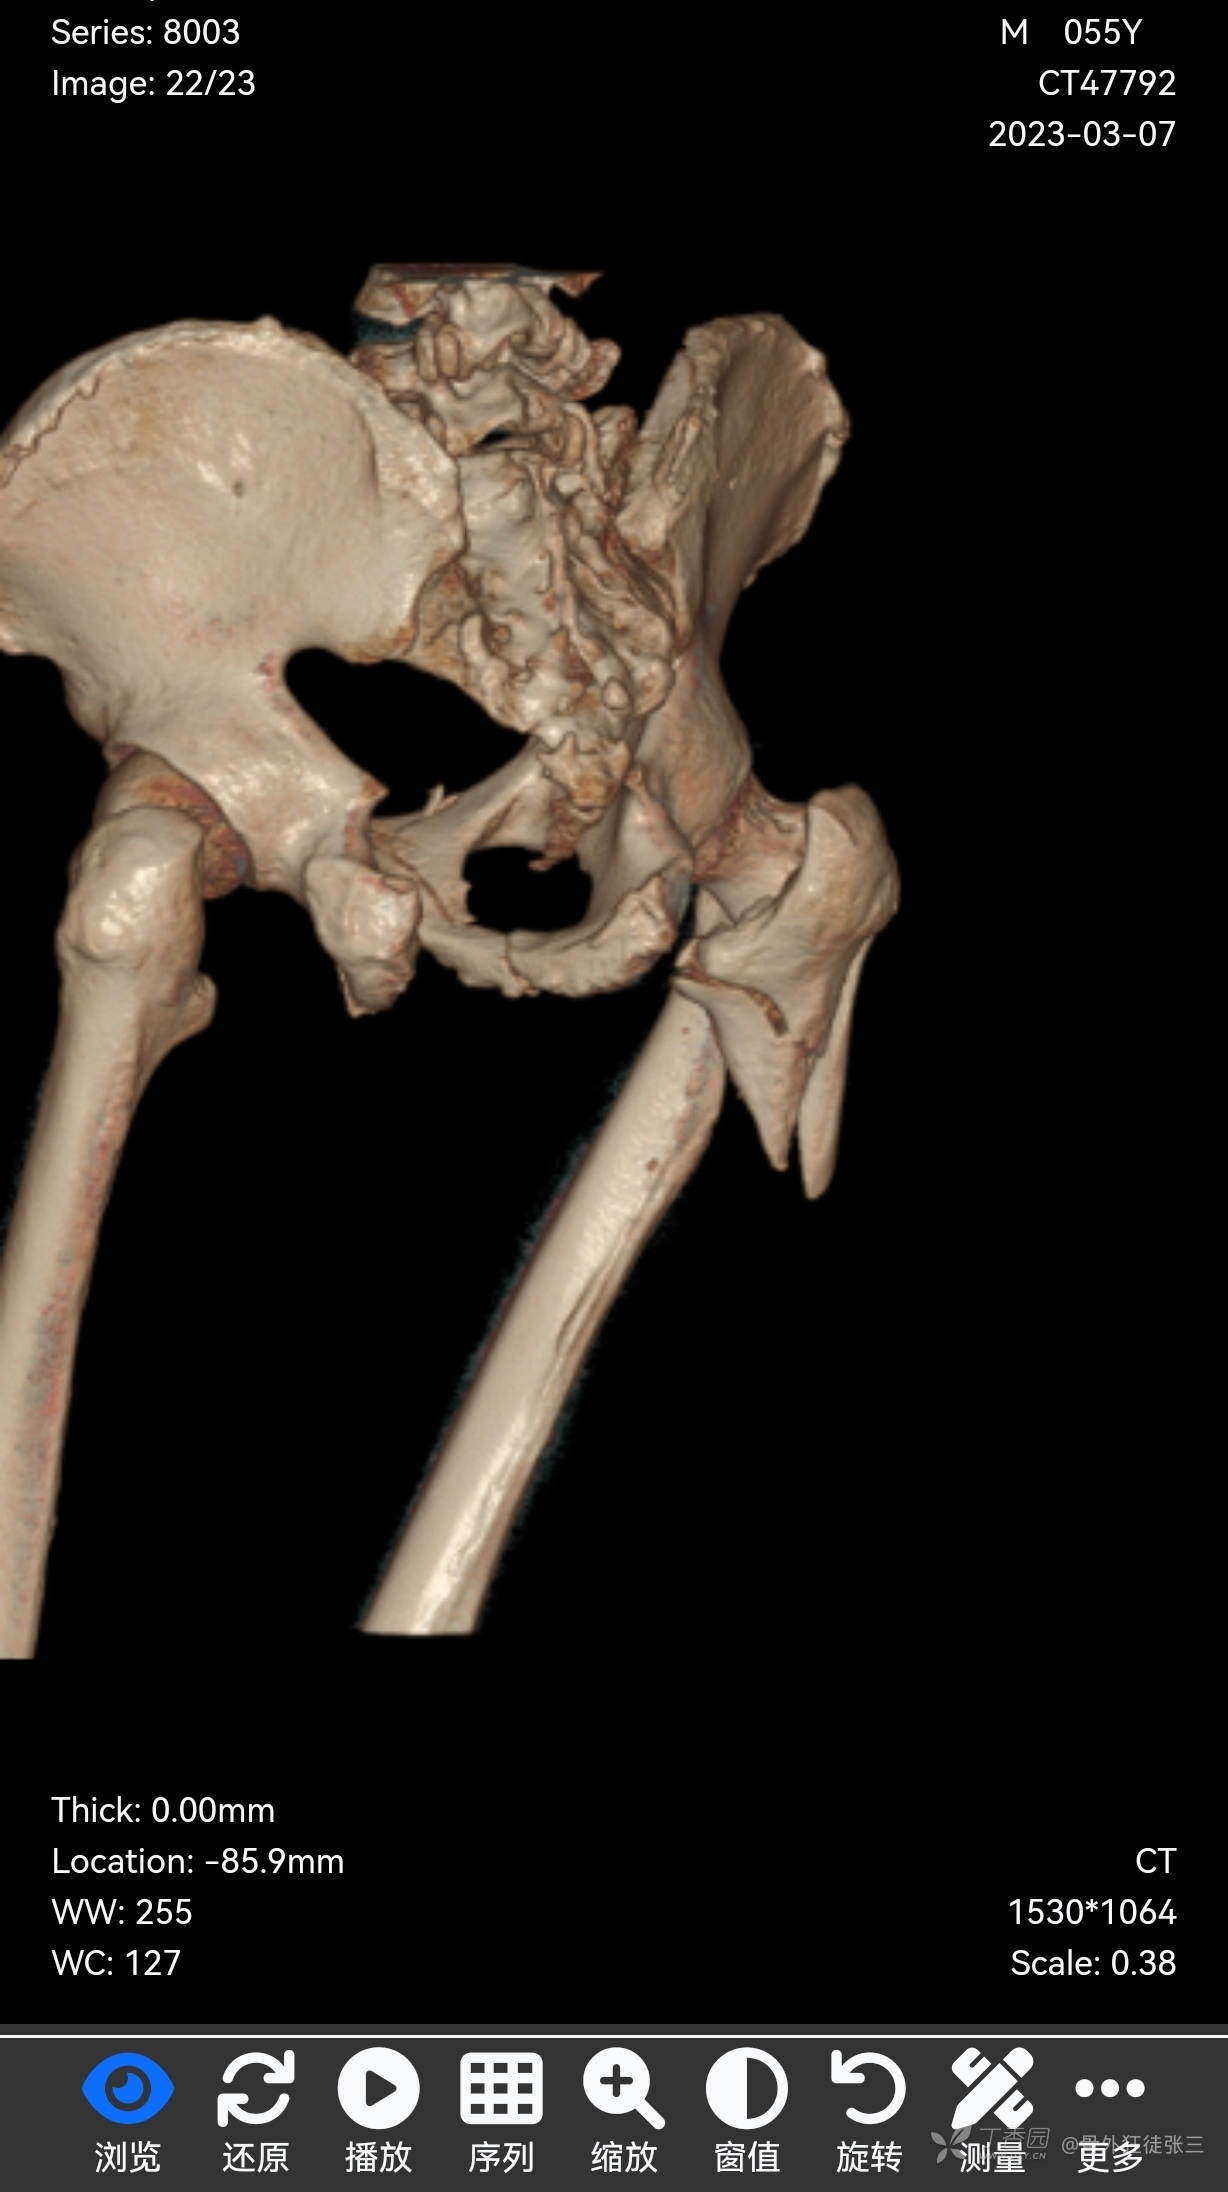

1,右股骨近端粉碎性骨折

8,骨盆多发骨折

CT示:右侧第5肋、胸骨、右侧髂骨、骶尾骨、右侧股骨颈、右股骨上段、左侧髋臼、双侧耻骨、双侧坐骨骨质连续性中断,部分断端错位,可见多发游离小骨片影。 右侧肘关节明显脱位,肱骨小头、肱骨滑车及桡骨小头多处骨质连续性中断,断端错位并分离,周围见多发游离小骨片影,周围软组织肿胀。 右侧舟骨、月骨骨质连续性中断,断端无明显错位。右侧豌豆骨向掌侧移位,可见骨质断裂。 左侧跟骨骨质连续性中断,断端错位,见多发游离小骨片影,周围软组织肿胀。右足诸骨骨质未见明显异常

4.骨盆多发骨折;右侧肘关节脱位并肱骨滑车、肱骨小头、桡骨小头粉碎性骨折